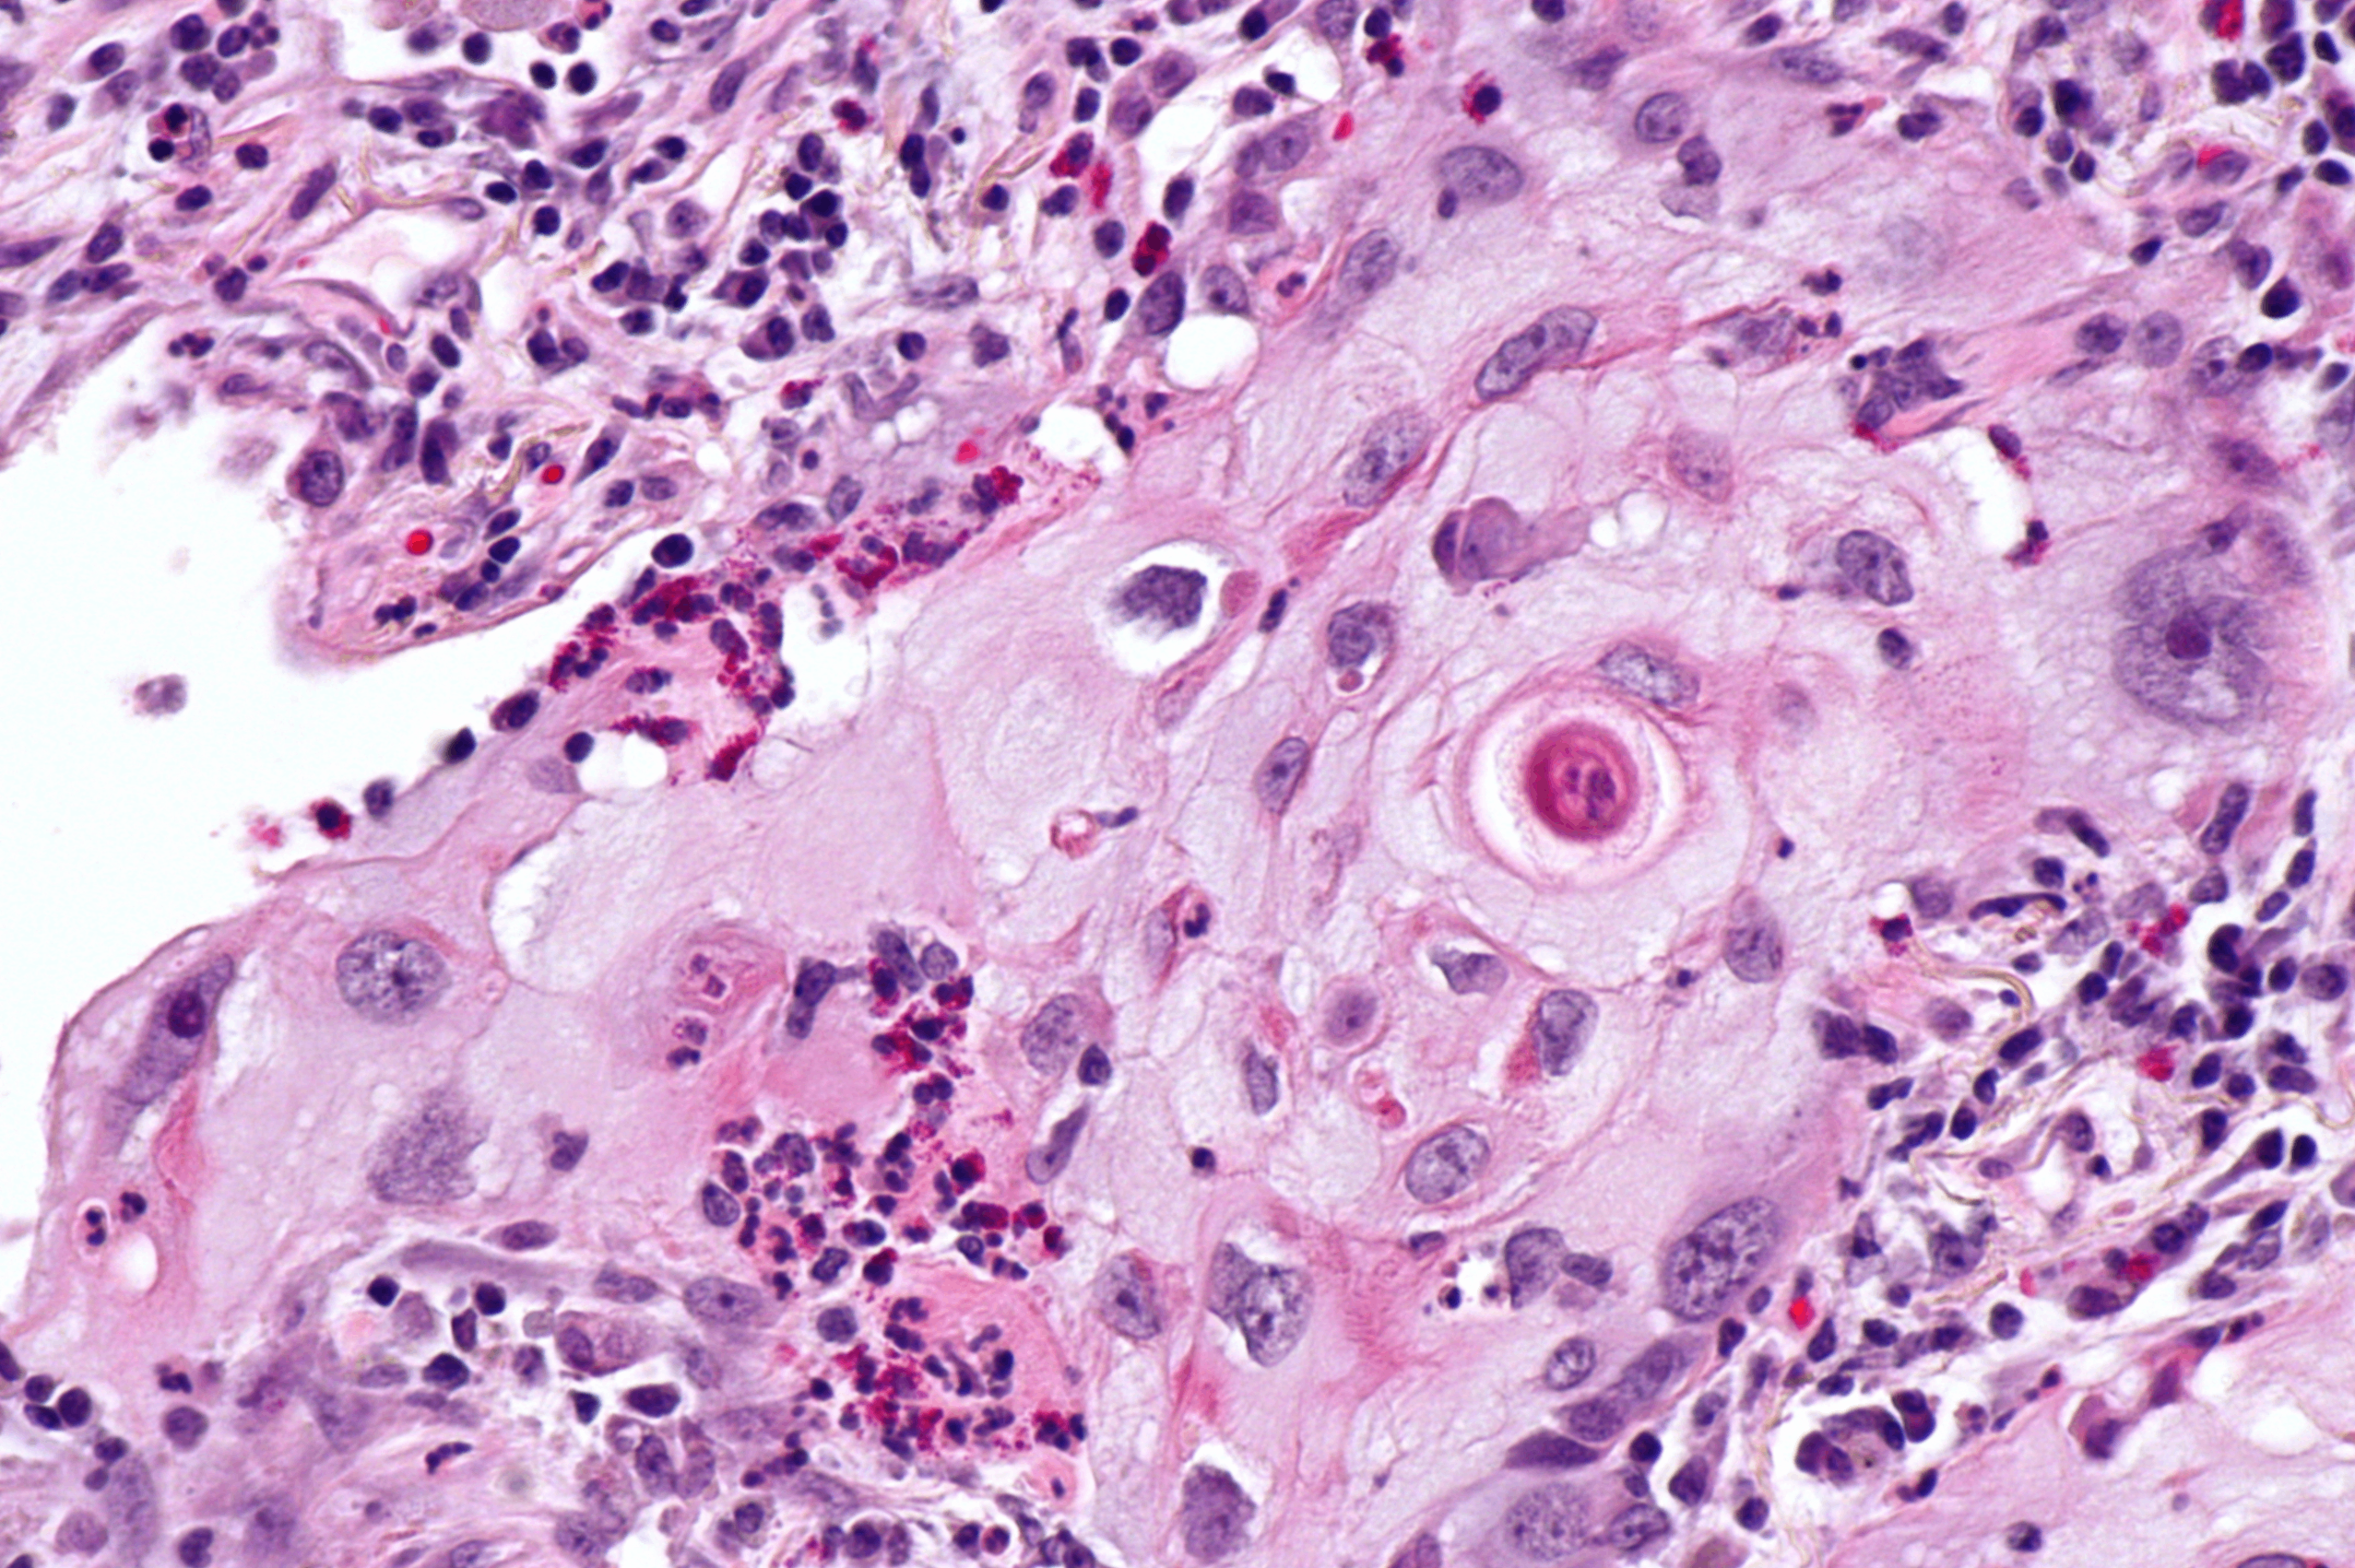

• 조직학적 특징:

- keratinization & keratin pearls

- intercellular bridges

- 종종 괴사와 공동(cavity) 동반

Lung squamous cell carcinoma, Wikimedia Commons

면역화학염색: p40, p63(+)